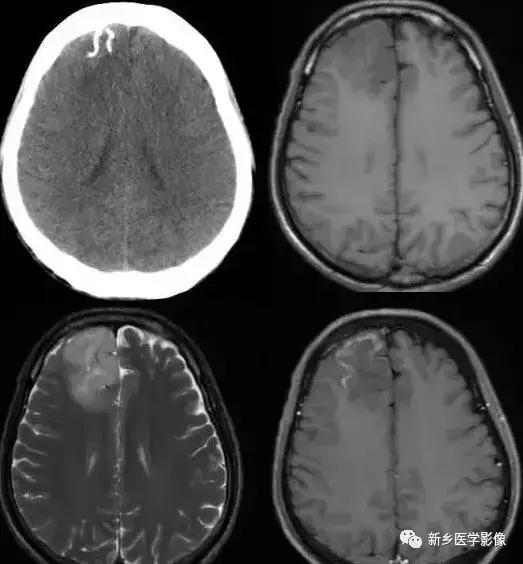

十八、脑三叉神经血管瘤病

又称颅颜面血管瘤病,Sturge-Weber综合征,绝大多数为散发。

CT:①钙化灶多为单侧性,始于枕叶,逐渐向前发展,居脑表浅部位,沿脑回呈曲线形或宽大锯齿状钙化;

②脑组织异常:局部脑组织坏死、胶质增生、钙化(斑点状、锯齿状),脑萎缩,脑皮质萎缩以枕叶萎缩明显,亦可累及整个大脑半球,脑沟增宽,但脑室不扩大;

③患侧颅骨增厚,头颅不对称;

④软脑膜血管畸形,增强扫描可见脑回状强化;脑深部异常引流经脉;

⑤75%病例同侧脉络丛增大,且显著强化。